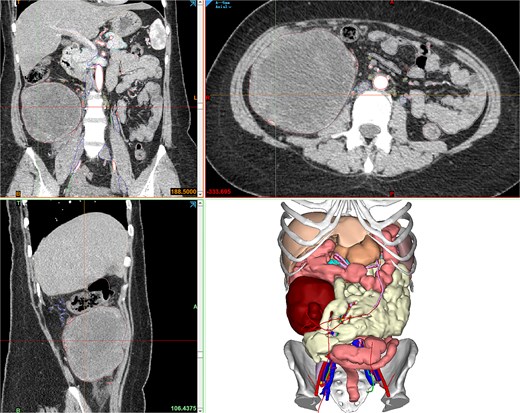

Contrast-enhanced abdominopelvic computed tomography (CT) (20 August 2024) identified a heterogeneous, hypodense mass (12 × 10.5 × 8.5 cm) arising from the ileocecal region, partially encasing the appendiceal base and colonic wall. Pelvic magnetic resonance imaging (MRI) further delineated the mass’s origin from the terminal ileum, showing adherence to the ileocolic vasculature without invasion of adjacent organs (Fig. 1). To refine surgical planning, a patient-specific 3D-printed model was generated using Mimics23 software (Materialize NV), which highlighted critical anatomical relationships, including compression of the ileocolic artery and proximity to the right ureter (Fig. 2).

Mimics23 3D model (3-Matic®15 simulation of surgical margins). Blue arrow: ileocecal region; yellow arrow: appendix.